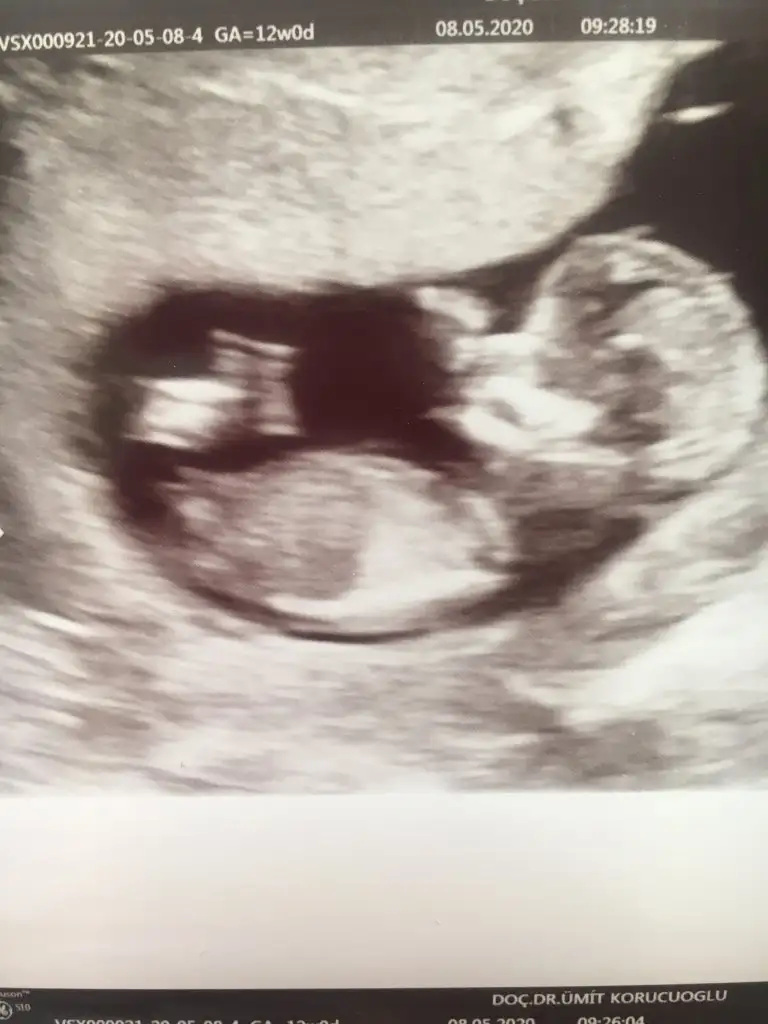

Merhaba bize de bir tahmininiz olur mu 🙏🏻? 12 haftalık usg

Eklentiler

• CAB8A84D-896C-4A10-A9BA-C3AB79B36979.webp

CAB8A84D-896C-4A10-A9BA-C3AB79B36979.webp

25 KB · Görüntüleme: 51